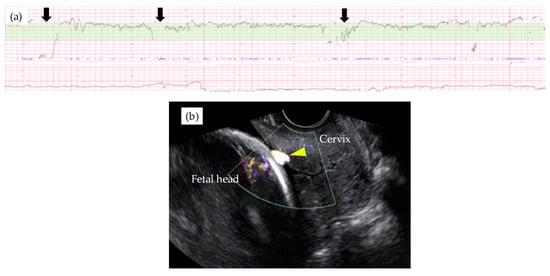

Figure 2. Abnormal fetal heart rate patterns (a) in a type 1 VP case with relatively large arterial vasa previa at 29th GW (b). Note that fetal heart rate decelerations were observed without uterine contraction (black arrown in Figure 2a) and relatively thick velamentous vessel was identified by the trans-vaginal ultrasound scan (yellow arrow head in Figure 2b).

Table 3 shows the results of management and operative outcomes. In 31 cases (56.4%), including three twin pregnancies, tocolytic therapy was necessary (ritodrine hydrochloride and/or magnesium sulfate), and a steroid for fetal lung maturation was given in 9/13 cases (69.2%) delivered before the 34th GW. An abnormal fetal heart rate pattern without uterine contractions was detected in one case in the type 1 group, and this case exhibited a relatively thick artery near the internal ostium (Figure 2). Cervical cerclage via the McDonald technique was performed in two cases in the type 1 group. One of these cases was a singleton pregnancy at 20th GW and a cervical length of 2.1 cm, delivered by CS at 33rd GW. The other was a monochorionic-diamniotic pregnancy case at 20th GW and a cervical length of 1.7 cm, delivered by CS at 31st GW; this patient had a previous history of preterm singleton delivery at 34th GW. Blood flow of fetal vessels was confirmed post-cerclage in both cases (Figure 3). Resolution was observed in 12 cases (21.8%) in total. An emergent CS was performed in 25 cases with increased uterine contractions and in one case with an indication of hypertensive disorder of pregnancy; none of these cases experienced the premature rupture of membranes. Although the Ward technique was more frequently used in the non-type 1 group, the details as to operative outcome showed no significant difference between the two groups. The transection of the placenta to approach the fetus was not used in any of the cases. All cases underwent a cesarean section, even in those cases of resolution of VP.